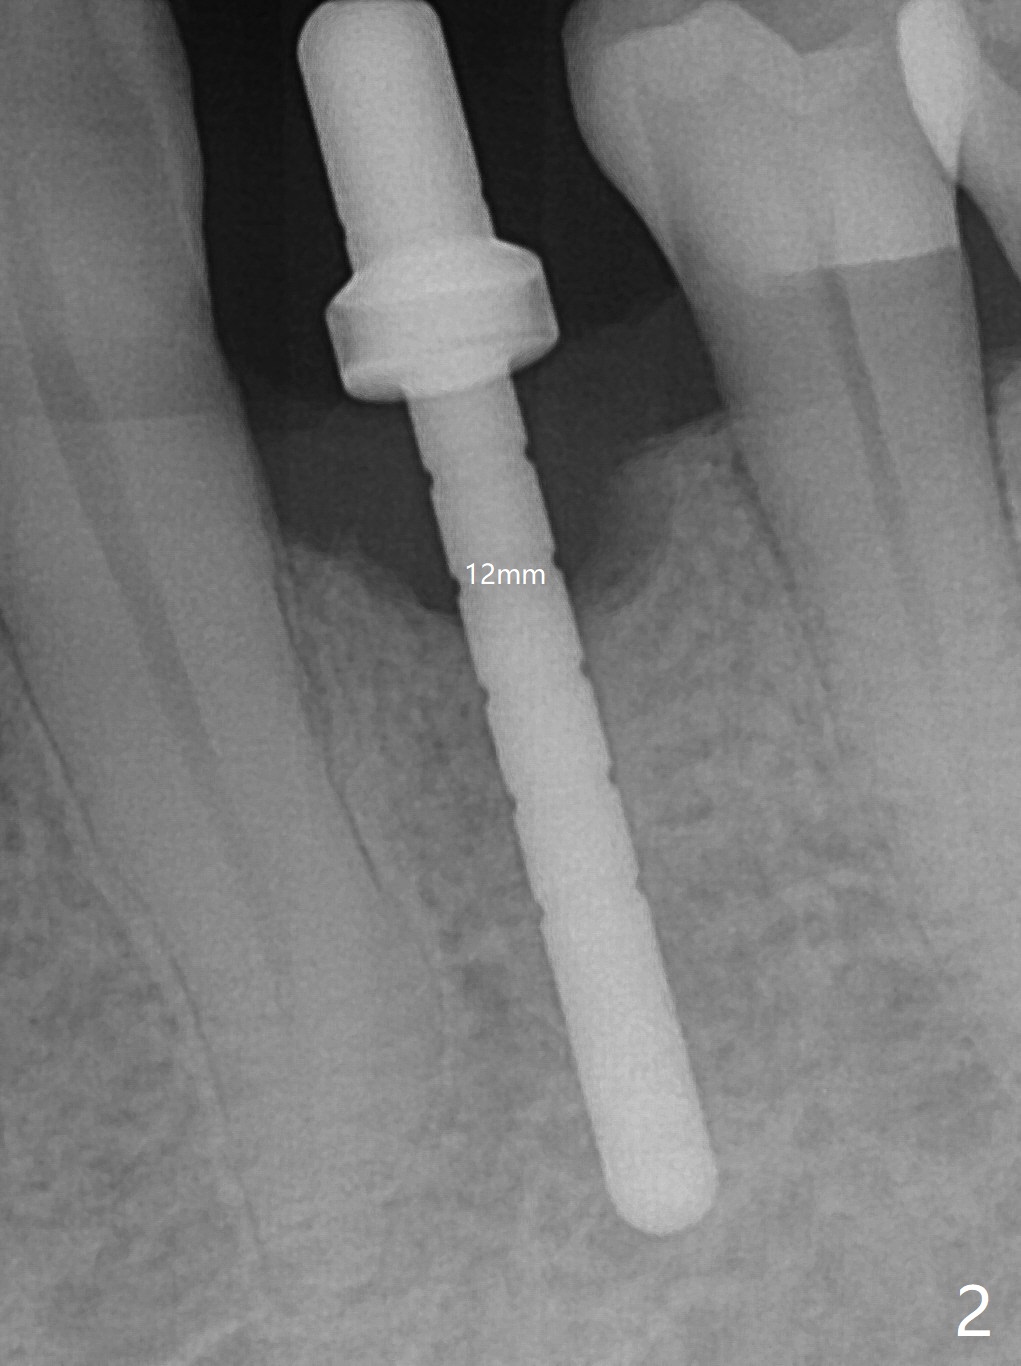

After incision at #21 (Fig.1) and flap elevation, the narrow ridge is reduced and initial osteotomy is made (Fig.2,3). Following moving the osteotomy distal, a 3x12(4) mm 1-piece implant is placed with >35 Ncm (Fig.4-6). Vanilla Graft is placed in the most concave buccal defect (Fig.1,4 *) and over the ridge reduction area (Fig.6 *). No bone loss is observed 3 months postop (Fig.7).